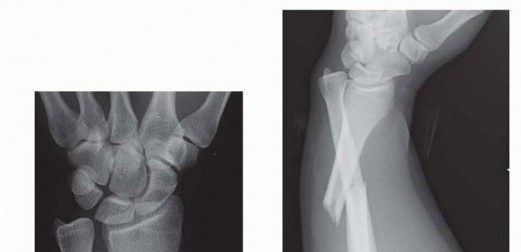

K-Wire Fixation of Distal Radius Fractures with and without External Fixation

Intramedullary and Dorsal Plate Fixation of Distal Radius Fractures

Arthroscopic Reduction and Fixation of Distal Radius and Ulnar Styloid Fractures